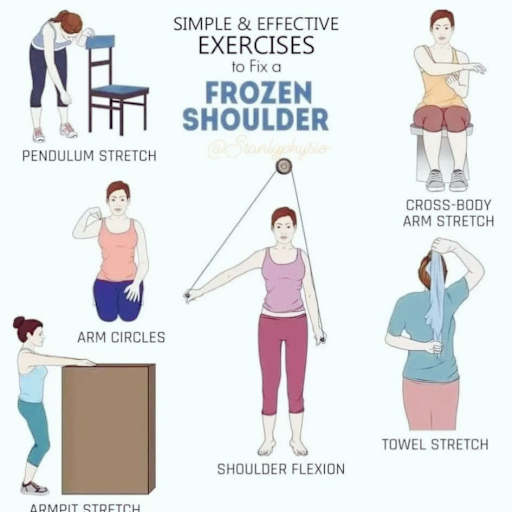

Women demonstrating pendulum stretch, cross-body arm stretch, arm circles, shoulder flexion, armpit stretch, and towel stretch exercises

Women demonstrating pendulum stretch, cross-body arm stretch, arm circles, shoulder flexion, armpit stretch, and towel stretch exercises

A reabilitação é onde eu, como fisioterapeuta, entro de cabeça no processo. Depois que o médico define o diagnóstico e o tratamento (conservador ou cirúrgico), a missão passa a ser devolver ao paciente a função plena do ombro: amplitude de movimento completa, força muscular adequada, estabilidade articular e confiança para retomar suas atividades.

Na fase inicial, o foco é o controle de dor e edema, a proteção da região lesionada e a manutenção da mobilidade das articulações adjacentes (cotovelo, punho e mão). Na fase intermediária, começa a recuperação da amplitude de movimento do ombro com exercícios passivos e ativo-assistidos. Na fase avançada, o fortalecimento muscular e o treino funcional tomam o protagonismo.

A segunda fase, ou fase de mobilidade, começa quando o médico libera a retirada da tipoia, geralmente entre 4 e 6 semanas. Eu inicio com exercícios pendulares (o braço balança como um pêndulo com o corpo inclinado para frente), que promovem mobilização suave da articulação glenoumeral sem estresse sobre o foco de fratura. Progressivamente, introduzo movimentos ativo-assistidos de flexão, abdução e rotações.

Na terceira fase, a de fortalecimento, o paciente já tem boa amplitude de movimento e o foco muda para a recuperação de força . Exercícios com faixa elástica, halteres leves e resistência manual são introduzidos gradualmente. Eu trabalho todos os grupos musculares do complexo do ombro: rotadores externos e internos, deltoide, trapézio, serrátil anterior e romboides.

A quarta fase é a de retorno funcional. Aqui, os exercícios simulam as atividades que o paciente precisa realizar no dia a dia ou no esporte. Se o paciente é ciclista, praticamos apoio de peso sobre as mãos e reações de proteção. Se é jogador de futebol, trabalhamos quedas controladas e impactos progressivos. A especificidade do treino é fundamental para um retorno seguro.

Após o período de proteção, a mobilização do ombro é iniciada de forma gradual. Começo com movimentos abaixo de 90 graus de flexão e abdução, porque movimentos acima desse limite aumentam o estresse sobre a articulação acromioclavicular. Com o passar das semanas e a melhora dos sintomas, vou ampliando o arco de movimento até atingir a amplitude completa.

O fortalecimento muscular é o pilar da reabilitação dessa lesão. Músculos como trapézio superior, deltoide posterior e rotadores externos do ombro atuam como estabilizadores dinâmicos da articulação acromioclavicular. Quando esses músculos estão fortes, compensam a perda de estabilidade ligamentar e permitem que o paciente retome suas atividades sem dor.

Na fase avançada, exercícios em cadeia cinética fechada (apoio de peso sobre as mãos, flexões de braço modificadas) e exercícios pliométricos (que envolvem velocidade e potência) são incorporados. Essa progressão é essencial para atletas que precisam retornar a esportes de contato ou que exigem apoio de peso nos membros superiores.

O treino proprioceptivo merece atenção especial. A lesão ligamentar compromete os mecanorreceptores da articulação, que são responsáveis por informar ao cérebro a posição e o movimento da articulação no espaço. Exercícios em superfícies instáveis, com olhos fechados e com perturbações externas ajudam a restaurar essa capacidade e a prevenir novas lesões.